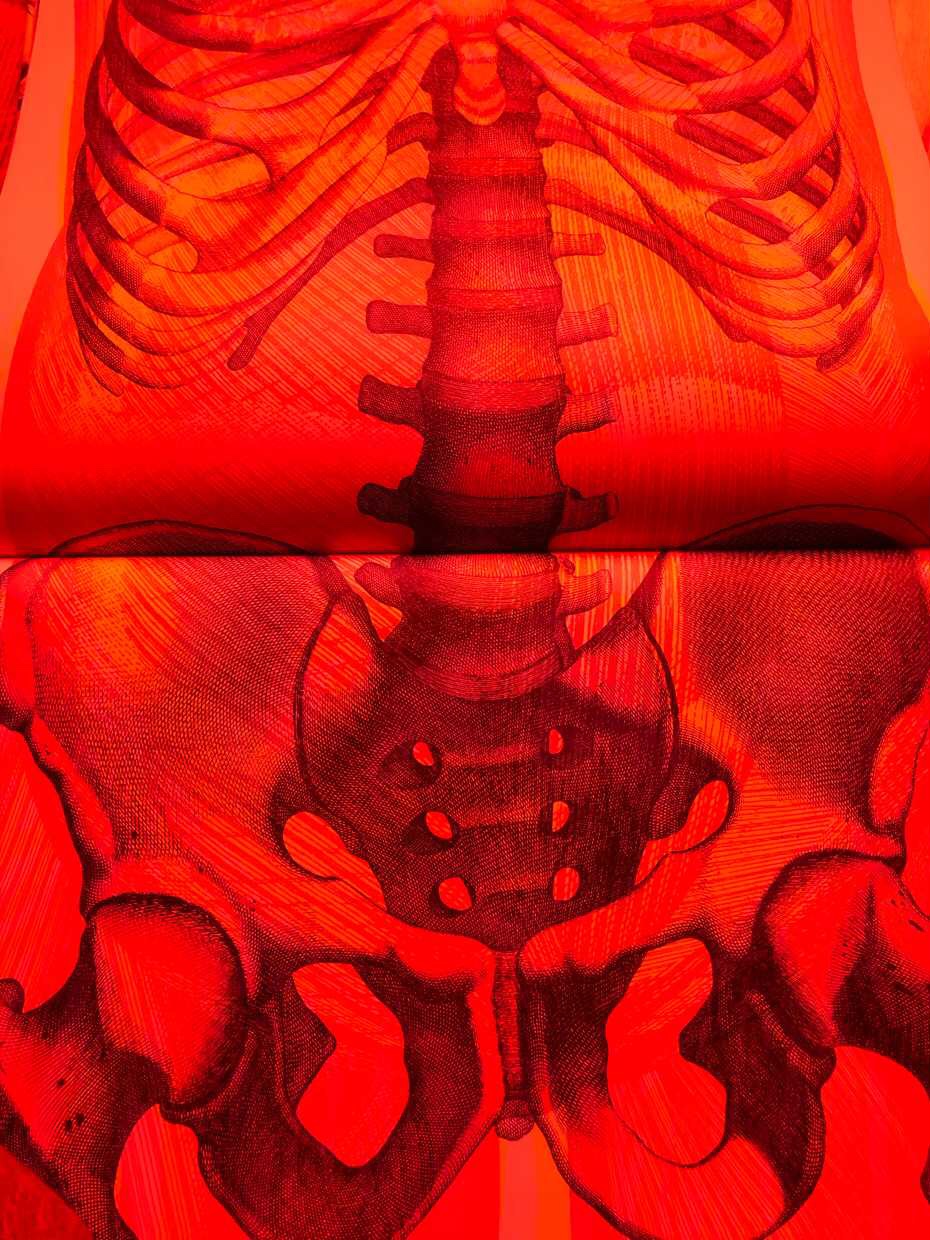

System filtrów staje się czymś znacznie więcej niż sztuczką, to czyni książkę wyjątkowym doświadczeniem. Kiedy zamieniamy kolory, widzimy niesamowity efekt odsłaniający szkielet pod ciałem i mięśniami.

Patrząc przez czerwony czytnik soczewki, odkrywamy szkielet ciała, zielona soczewka odkrywa mięśnie, a niebieska pokazuje narządy i naczynia krwionośne. Zauważyłam, że używając niebieskiej soczewki, obrazy są dość ciemne. Trzeba mocno wytężyć wzrok, aby coś dostrzec.